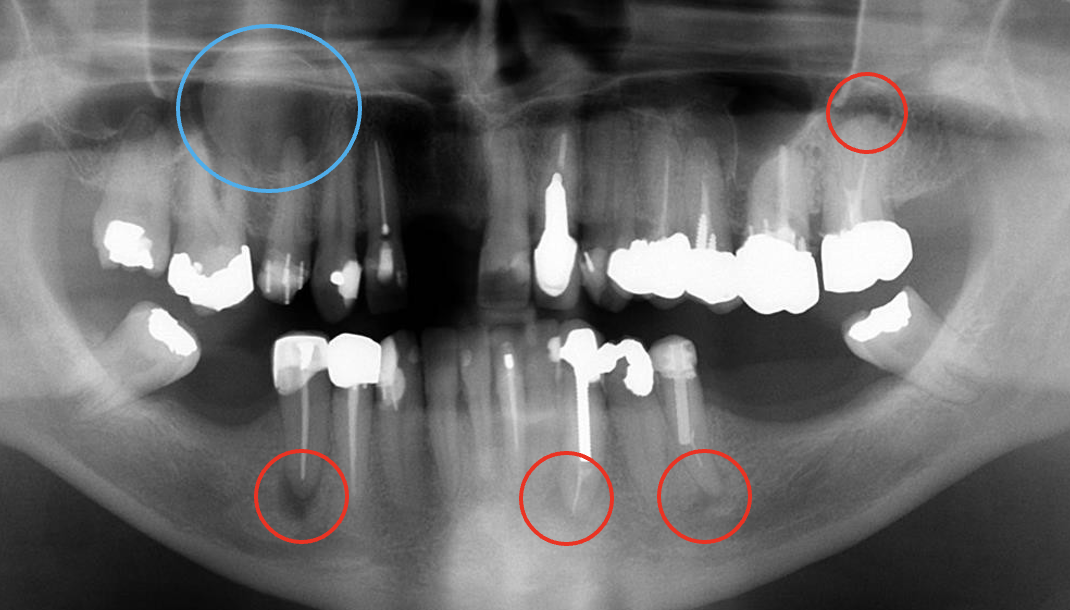

what do the red and blue circles indicate

red circles = periapical pathology

blue circle = cyst